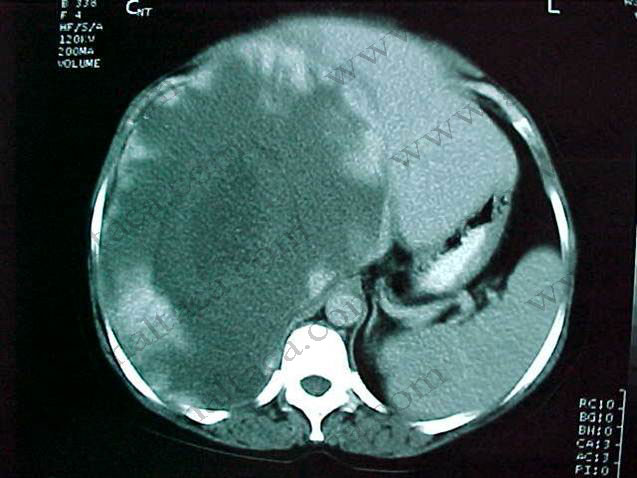

Karaciğer, safra kesesi, pankreas